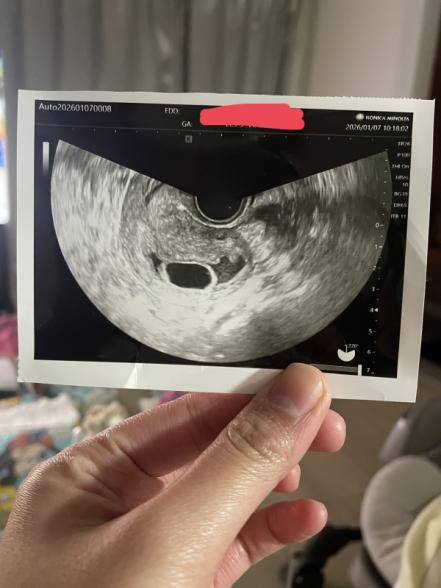

12/24に胎嚢が確認でき、2週間後にまたきてと言われて今日診察に行ったのですが、

胎嚢は見えるけど赤ちゃんは確認できないとのことでした。

妊娠8週目なので赤ちゃんの心拍が聞けると楽しみにしていたのですが、赤ちゃんが確認できないと聞かされ頭の中がパニックになりました。

8週で赤ちゃんが見えなかったということで、ご相談ですね。

そろそろ心拍も確認できる頃かと思っておられたところ、戸惑われたと思います。

これまでの月経周期を拝見すると平均31日となっていて、34日ほど開くこともあったようなので、排卵のタイミングがずれていた可能性はあるように感じました。

排卵の時期が遅れていて、着床までも時間がかかっていたこともありましたら、その分心拍が確認できないこともあると思いますし、診察時の角度によっても赤ちゃんの姿が見えないということも考えられるように思います。